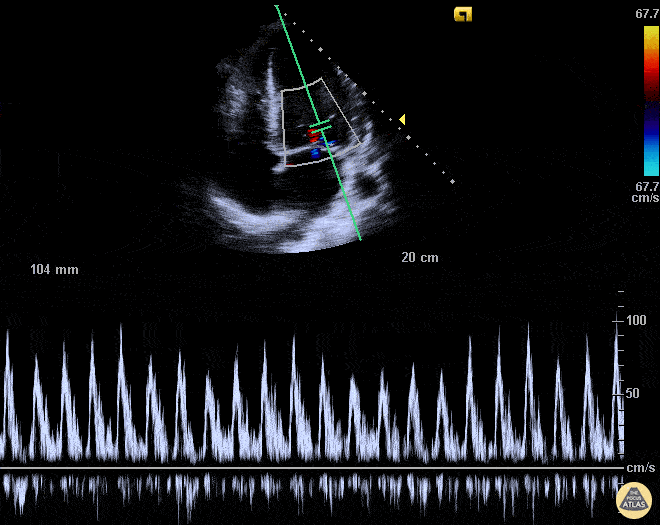

This patient presented with acute blood loss anemia and high output heart failure. Note the significant mitral valve inflow respiratory variation secondary to hypovolemia (not attributed to the trace pericardial effusion). This nicely illustrates potential mitral/tricuspid valve inflow variation in hypovolemic patients. Luka Petrovic, Chief Medical Resident Rutgers New Jersey Medical School @lukapetrovic89